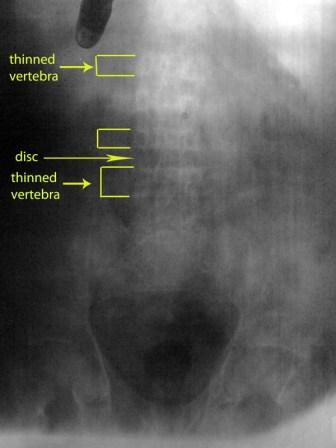

Male patient 40 year-old, chronic

renal failure, on regular dialysis complaining of gradual progressive

shortening of his height enough to change his clothes to be shorter.

Notice:- very faint bone density - thin vertebra